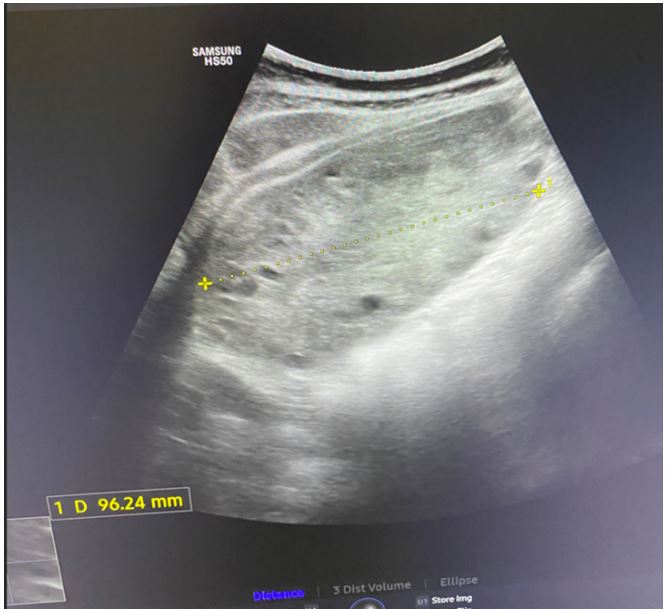

Transabdominal ultrasound identified intrauterine MCMA twin pregnancy. The right ovary measured 14x6.5x9.7 cm with multiple peripherally displaced ovarian follicles resembling a string of pearls (Figures 3 and 4). The left ovary measured 12x7x9.1 cm also with peripheral follicles and stromal oedema (Figure 5). In both ovaries, there was an absent doppler flow. In the region of the right adnexa, there was a collection of free fluid up to 8 mm (Figure 3). Umbilical arterial (UA) Doppler assessment was used in the surveillance of fetal well-being, which showed good fetal condition (Figures 6 and 7).

Figure 3: Abdominal ultrasound: The highly enlarged right ovary with ‘’String of pearl’’ phenomena, and a collection of free fluid on the far right.